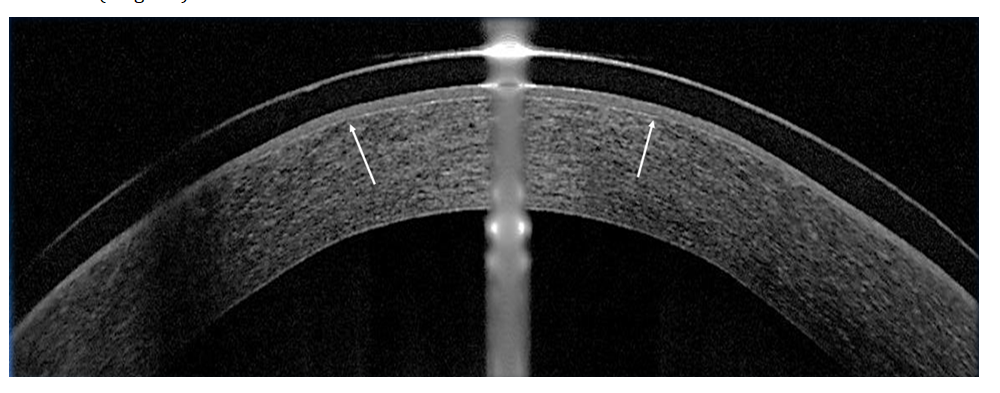

With this photokeratoablation technology, the quality of the ablative surface improved due to the formation of a Bowman-like membrane structure. On OCT of the cornea, such a membrane structure was detected only when its thickness exceeded 5 μm, which corresponded to the resolution of the device (Figure 4). OCT and densitometric studies showed an increase in optical density in the stromal layers adjacent to the ablation zone. In isolated cases, after 3-4 weeks, a gentle demarcation line was revealed (Figure 5). With corneal densitometry, an increase in optical density was observed in the stromal layers adjacent to the ablation zone. With prophylactic laser-induced crosslinking, the elastic properties of the cornea were not impaired. Visual and optical-refractive results of prophylactic crosslinking have been reviewed in previously published works [6,7].

Figure 4:Complete epithelialization under a contact lens 48 hours after TransPRK with riboflavin. In the ablation zone under the epithelium, a Bowman-like membrane structure is determined

Figure 5:The appearance of a gentle demarcation line a month after the operations TransPRK andFemtoLASIK with riboflavin.